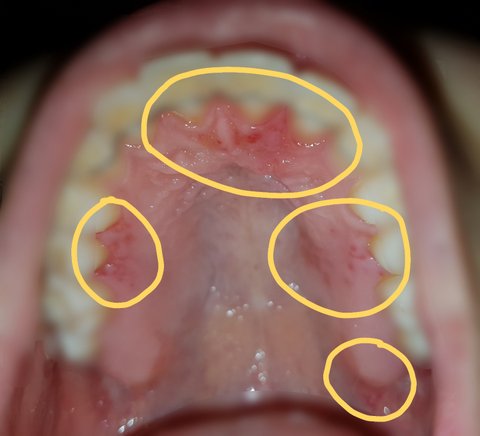

그리고 낮잠을 자고 일어나니, 가운데 윗 잇몸도 심각하게 붓고 오른쪽 윗 잇몸은 벗겨지고 있었으며, 전체적으로 발갛게 부어있었습니다.

다음은 피해사진입니다.

#피해자1

-4월 30일 월요일 낮

-4월 30일 월요일 밤

-5월 1일 화요일 아침